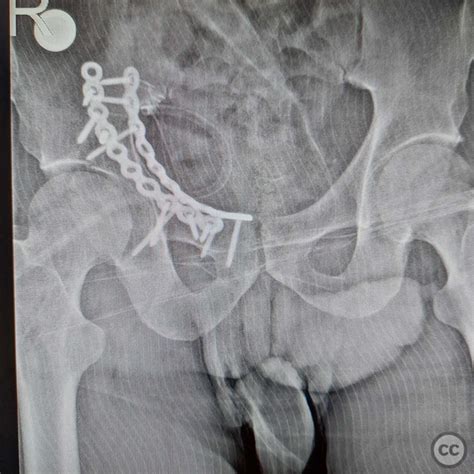

Open Reduction and Internal Fixation (ORIF) is the standard surgical approach for Fractures Of Acetabulum. The objective is to restore the smoothness of the joint surface and the stability of the pelvic ring. Surgeons use plates and screws to hold the bone fragments in place, allowing for earlier mobilization and a better long-term functional outcome.

💡 Note: Patients undergoing ORIF must strictly adhere to weight-bearing restrictions provided by their orthopedic surgeon, as premature loading can lead to hardware failure or secondary displacement of the fracture.